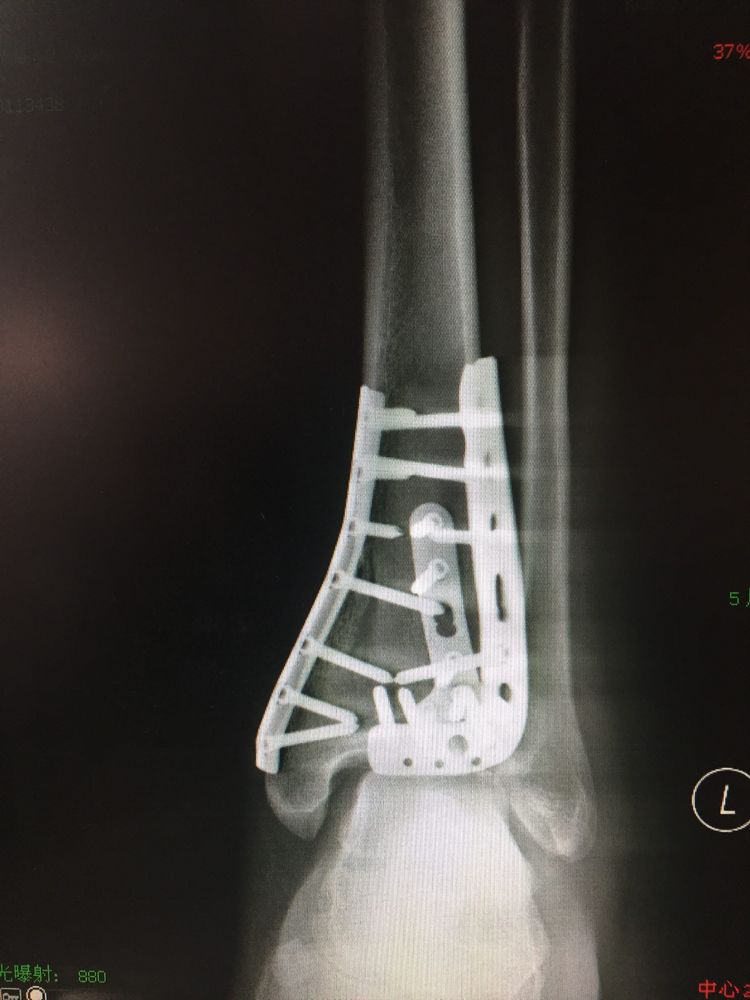

足踝创伤类手术是我学习交流的主战场。后踝骨折经外踝骨折掀起暴露复位的方法,后踝骨折需要板钉固定的情况,下胫腓前联合修复的方法,跟骨骨折撬拨复位要点,Pilon骨折复位的顺序,陈旧骨折复位的技巧等等,每一台手术都是一次难得的学习机会,受益匪浅。